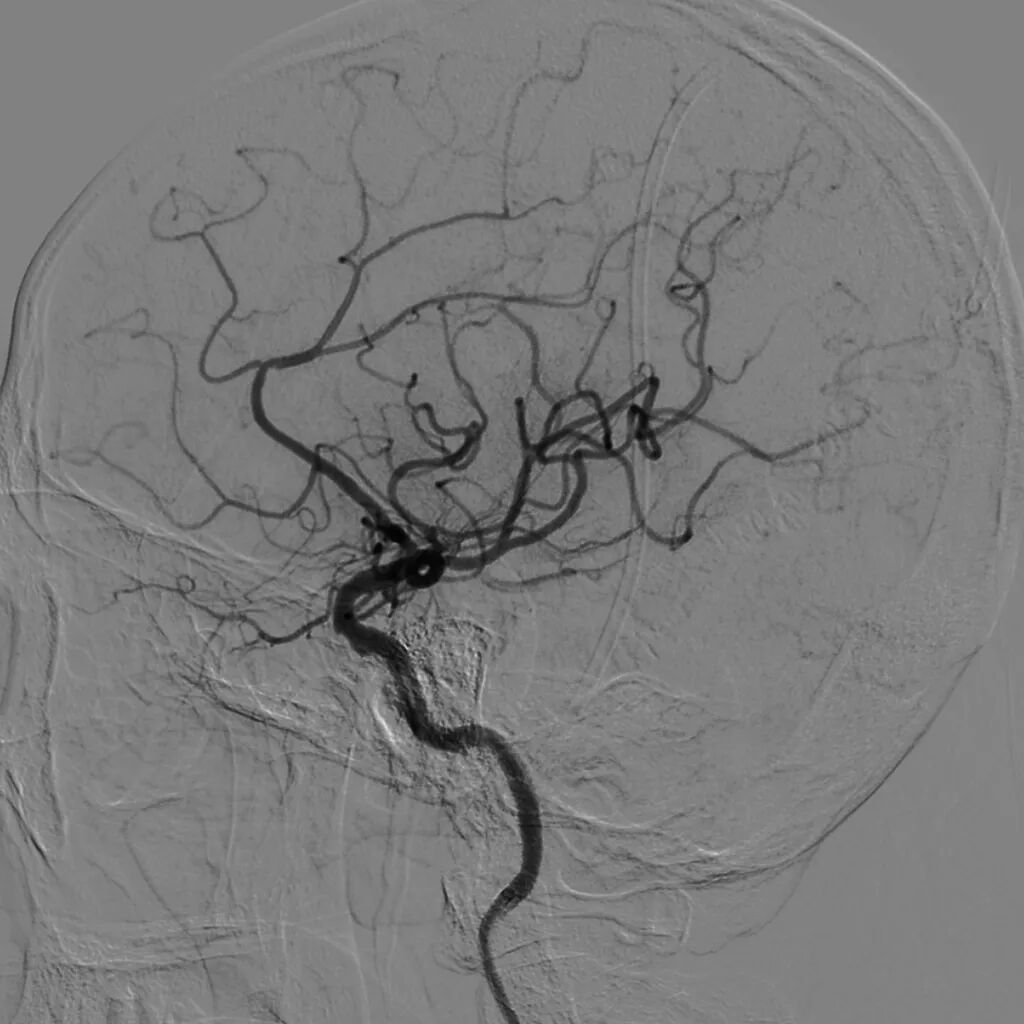

单弯导管辅助长泥鳅导丝置于LC1末端,交换Infinity长鞘至LC1,DSA:LM闭塞。

4*20mm Trevo ProVue取栓支架释放,5分钟后抽拉结合取栓,一次取栓,大脑中动脉完全再通。

大脑中动脉完全再通。